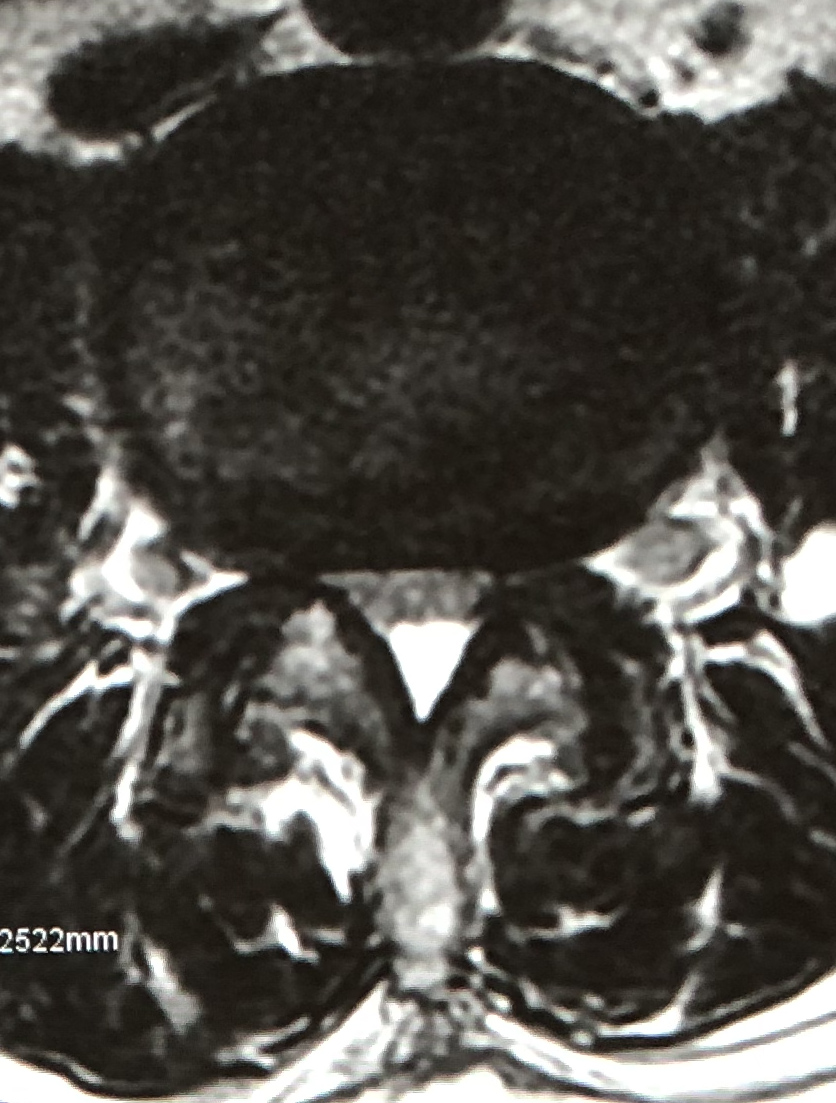

eXtreme Lateral Interbody Fusion(XLIF)は、主に左脇腹からの小皮切で腰椎に側方からアプローチし、脊椎前方に十分な骨移植を行ない脊椎の矯正固定を行なう手術方法です。脊柱管内には一切触れずにす椎間板の高さを増大させてすべりを矯正し、間接的な神経の除圧が可能です。

| 術前 | 術後 | |

| MRI |

|